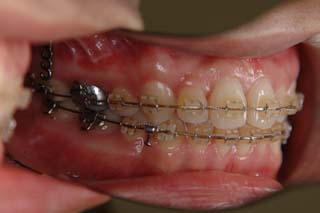

この症例では、目的外使用の オーソアンカー SMAPシステム が用いられています。

使用した主な装置名:TPB、マルチブラケット装置、オーソアンカー SMAPシステム

上顎前歯、下顎前歯の前突が見られます。大きな叢生は見られませんが、上下の口唇前突感も伴います。このような不正咬合を上下顎前突と言います。審美的な事もさることながら、歯軸の傾斜の問題から歯にかかるベクトルが良くない事、口唇の筋肉の緊張を強いるような不調和を示す事などから、不正咬合の一つとして考えられています。上顎前突傾向も伴っていますので、積極的に上顎前歯の後退を行う目的で、上顎に固定源となる 目的外使用の オーソアンカー SMAPシステム を装着しました。現在では、歯科矯正用アンカースクリュー(デュアルトップオートスクリュー、ISAアドバンスなど)といった、医療機器認証番号がある製品を用いることが多くなりました。